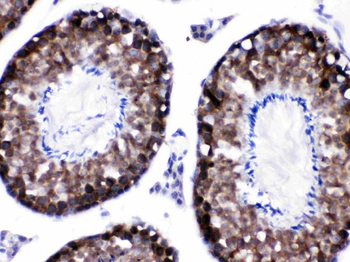

−| Tested Applications | ELISA, IHC |

| Dilution Range | IHC-P:1:20-1:200 |

| Immunogen | Recombinant Human Protein S100-A6 protein (1-90AA) |

| Target | S100A6 |

S100A6 Antibody (orb239280)